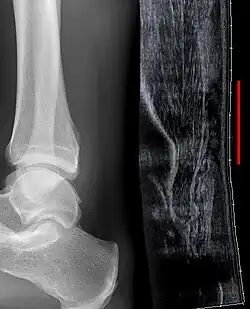

Although a tear may be diagnosed by history and physical exam alone, an ultrasound scan is sometimes required to clarify or confirm the diagnosis. Once diagnosis is made, ultrasound imaging is an effective way to monitor the healing progress of the tendon over time. An ultrasound is recommended over MRI and MRI is generally not needed.[12][15] Both MRI and ultrasound are effective tools and have their strengths and limitations. However, when it comes to an Achilles tendon tear, an ultrasound is usually recommended first because of convenience, quick availability, and cost.[16]

Imaging

Ultrasonography can be used to determine the tendon thickness, character, and presence of a tear. It works by sending harmless high frequencies of sound waves through the body. Some of these sound waves reflect back off the spaces between fluid and soft tissue or bone. These reflected images are analyzed and created into an image. These images capture in real time and are helpful in detecting movement of the tendon and visualizing injuries or tears. This device makes it possible to identify injuries and observe healing over time. Ultrasound is inexpensive and involves no harmful radiation. It is operator-dependent and so requires a level of skill and practice for it to be used effectively.[16]

Radiography can also be used to indirectly identify Achilles tendon tears. Radiography uses X-rays to analyze the point of injury. This is not very effective at identifying soft tissue injuries. X-rays are created when high energy electrons hit a metal source. X-ray images are acquired by utilizing the different densities of the bone or tissue. When these rays pass through tissue they are captured on film. X-rays are generally best for dense objects such as bone while soft tissue is shown poorly. Radiography is not the best for assessing an Achilles tendon injury. It is more useful for ruling out other injuries such as heal bone fractures.[15]